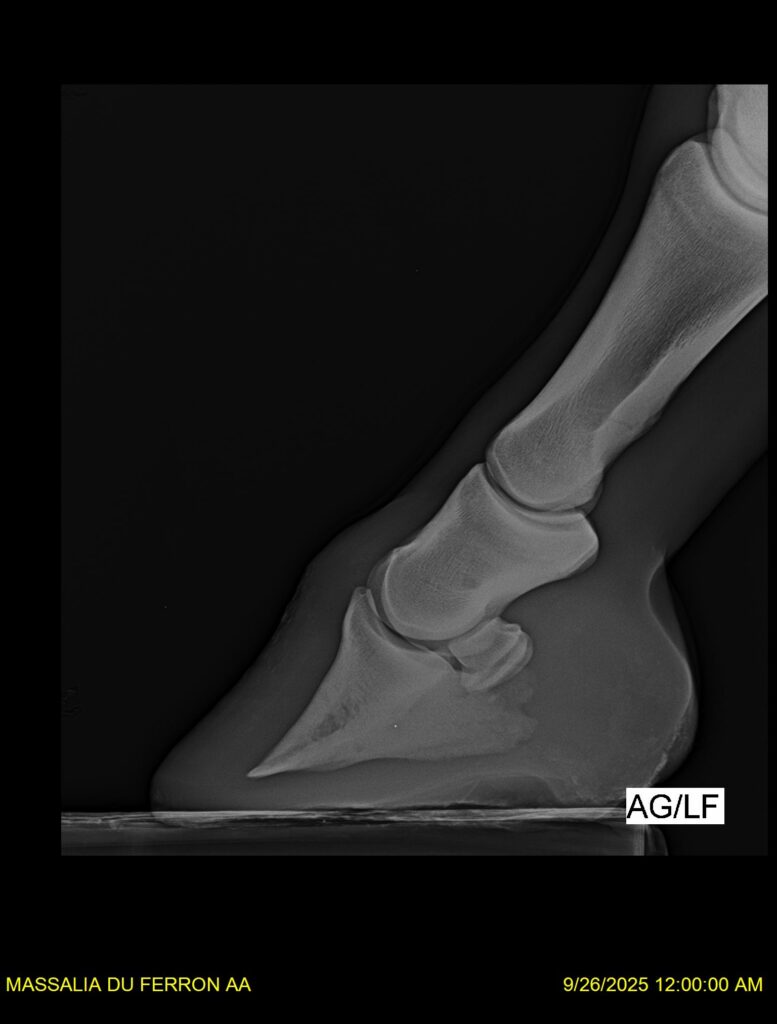

MASSALIA DU FERRON, jument qui prendra 4 ans par PRESTIGE KALONE x TRESOR DU RENOM. Un mental en or et un véritable sens de la barre ! Facile d’accès ! Bonne énergie et bons moyens. Souche moderne et très intéressante. Transport OK, maréchalerie OK, santé RAS, Bilan clichés radios OK.

RADIOS et COMPTE RENDU